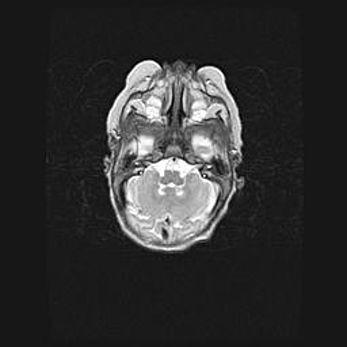

Мальформация Денди-Уокера. Киста задней черепной ямки.

Агенезия мозолистого тела.

Возраст: 2,5 месяца

Вес: 2420 г

Пол: женский

Окружность головы: 37 см

Срок гестации: 32 недели

Мальформация Денди—Уокера — редкий вид патологии ЦНС, представляющий собой врожденный порок развития каудального отдела ствола и червя мозжечка, ведущий к неполному раскрытию срединной (Мажанди) и латеральных (Лушка) апертур IV желудочка мозга. Для этогно синдрома характерна триада симптомов: гипотрофия червя мозжечка и/или полушарий мозжечка, кисты задней черепной ямки, гидроцефалия различной степени. В 70% случаев порок сочетается и с другими аномалиями головного мозга, в частности с агенезией мозолистого тела.